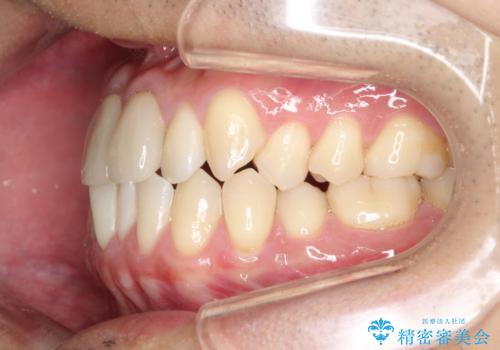

上下のがたつきをインビザラインで目立たない矯正

- 前歯のガタガタを主訴に来院されました。

上下の前歯のガタガタと左上の歯が反対にかんでいる状態でした。

上下の歯と歯の間をわずかに削り並べる計画としました。

目立たずに歯並びがよくなり、前歯に装着されたセラミックも壊さずに矯正治療が終了し満足していただけました。